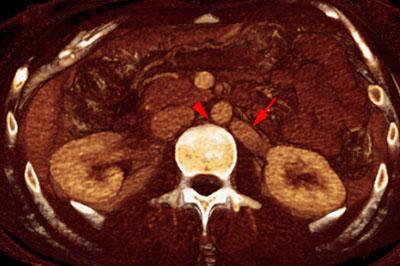

Síndrome del cascanueces retroaórtico